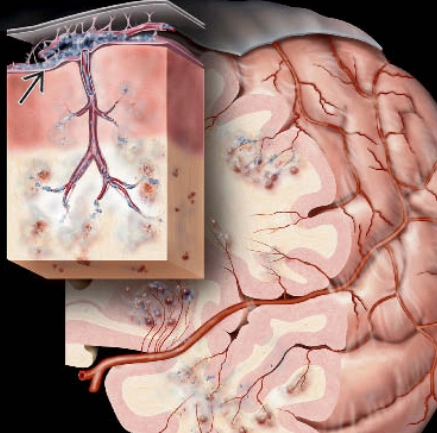

Di căn nhu mô não (Parenchymal metastases)